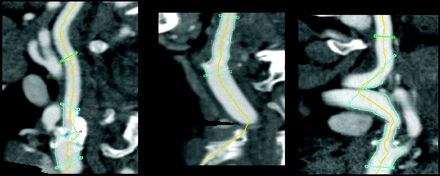

Retrospective analysis of individual cases with large differences revealed that deviations were caused by the semiautomated method due to either incorrect centerlines or lumen segmentation errors because of the presence of calcifications. In total, 56 of 354 (16%) centerlines were considered incorrect, mainly due to running through calcifications. Figs 4 and 5 show examples in which the centerline runs along the calcifications and skips part of a very tortuous artery. Such deviations were generally accepted in all 4 semiautomatic stenosis measurement runs. In several cases, the semiautomated method overestimated the minimal lumen due to the presence of calcifications (Fig 6).

Examples of incorrect centerlines. Left, The centerline follows the calcium rather than the lumen; Middle, the centerline follows a part of the bone; Right, the centerline misses a part of the artery and crosses the tortuous artery.